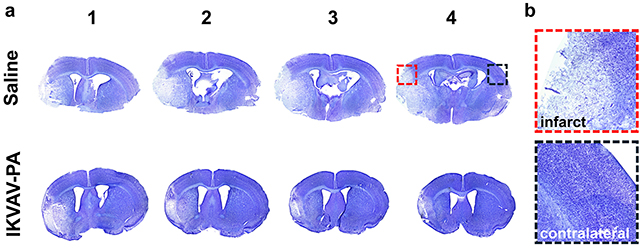

Compared to untreated mice, those given the injected biomaterial after the restoration of blood flow to the brain showed less damage to brain tissue, fewer signs of inflammation, and fewer signs of harmful immune responses.